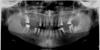

Иоанна Опубликовано 15 января, 2010 Поделиться Опубликовано 15 января, 2010 Уважаемые спецы, помогите советом. Перед Вами жертва стоматологии начала 90-х.Какие, по Вашему мнению, есть варианты протезирования правых верхних 4, 5, 6-ки?Предлагалось:1) мост с коронками на 2 и 3-ке;2) имплантация 4 и 5-ки, от которой мост к 7-ке. но при этом он не просто монолитно соединяется с 7-кой, а как-то, в моем представлении, шарнирно, сбоку в нее входит. Этот вариант мне больше нравится, но, видимо, своей загадочностью.На всякий случай - я из Питера. Ссылка на комментарий

Bier Опубликовано 15 января, 2010 Поделиться Опубликовано 15 января, 2010 протезирование делается не с одной стороны, а во всей полости рта. ни один из приведенных способов не имеет права на жизнь. право верх - синуслифтинг и имплантация в позиции 16, (15?), 14 зубов. с остальными сегментами тоже надо разбираться. Ссылка на комментарий

Иоанна Опубликовано 15 января, 2010 Автор Поделиться Опубликовано 15 января, 2010 Bier, cпасибо за ответ. Протезировать, разумеется, буду все и сразу (после долечивания еще 2 зубов). С тремя другими участками все, как будто бы, ясно - коронки, мосты... Можно узнать, почему не имеет права на существование второй вариант& Знаю, что импланты с собственными зубами в мост не объединяются. Поэтому и предлагается такая конструкция, которая, как мне объяснили, будет обеспечивать неподвижность имплантов при естественной подвижности 7-ки. Ссылка на комментарий

Иоанна Опубликовано 15 января, 2010 Автор Поделиться Опубликовано 15 января, 2010 Спасибо. Но мне еще сказали, что над 6-кой кости "маловато будет". Ссылка на комментарий

Иоанна Опубликовано 15 января, 2010 Автор Поделиться Опубликовано 15 января, 2010 Спасибо. "Когда же Вы будете читать то, что Вам пишут??? Написали же уже один раз" Но зачем проявлять такое нетерпение в ответ на просьбу помочь? Мы ведь в неравном положении, зачем его еще и подчеркивать: Вы - спецы, а мы (пациенты) - обречены Вам доверять и надеяться на чудо, которое Вы с нами сотворите. Поэтому поясняю происхождение своей предыдущей ремарки: мне объяснили, синус-лифтинг в моей ситуации бессмыслен, так как мало костной ткани. Ссылка на комментарий

Doc Опубликовано 15 января, 2010 Поделиться Опубликовано 15 января, 2010 Спасибо. "Когда же Вы будете читать то, что Вам пишут??? Написали же уже один раз" Но зачем проявлять такое нетерпение в ответ на просьбу помочь? Мы ведь в неравном положении, зачем его еще и подчеркивать: Вы - спецы, а мы (пациенты) - обречены Вам доверять и надеяться на чудо, которое Вы с нами сотворите. Поэтому поясняю происхождение своей предыдущей ремарки: мне объяснили, синус-лифтинг в моей ситуации бессмыслен, так как мало костной ткани. Проявляю ангельское терпение и третий раз говорю - синуслифтинг там возможен, мало того, его НУЖНО делать! Если кто-то не может сделать там синус, то найдите того, кто сможет, только и всего! Ссылка на комментарий